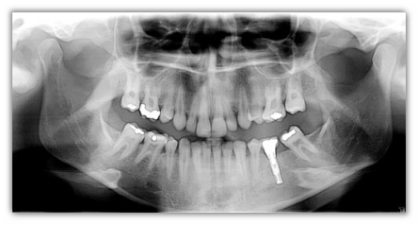

Kodak panoramico digitale Kodak 8000

Epitomo della semplicità, il sistema KODAK 8000 realizza in pochi secondi immagini panoramiche con una nitidezza e un'esposizione ottimali. Grazie all'immediata disponibilità delle immagini extraorali, il sistema consente di formulare diagnosi accurate contestualmente all'esame e di comunicare facilmente le varie possibilità di trattamento ai pazienti.

Consigliato per normali esami dentari e valutazioni degli impianti, ma anche per chirurgie del cavo orale, quali ad esempio pianificazioni delle estrazioni, esami del rapporto corona-radice nonché dell'articolazione temporomandibolare.

Utilizzate il sistema KODAK 8000 per ottenere immagini panoramiche digitali nitide, che consentono di formulare diagnosi precise. Dalle immagini dell'articolazione temporomandibolare a quelle seno-mascellari, l'intuitiva unità radiografica per immagini panoramiche digitali produce l'immagini di elevata qualità, necessaria per garantire diagnosi accurate direttamente in clinica, senza tempi di attesa. Possiamo affermare che si tratta di uno dei sistemi di imaging panoramico più facili da usare e convenienti oggi disponibile.